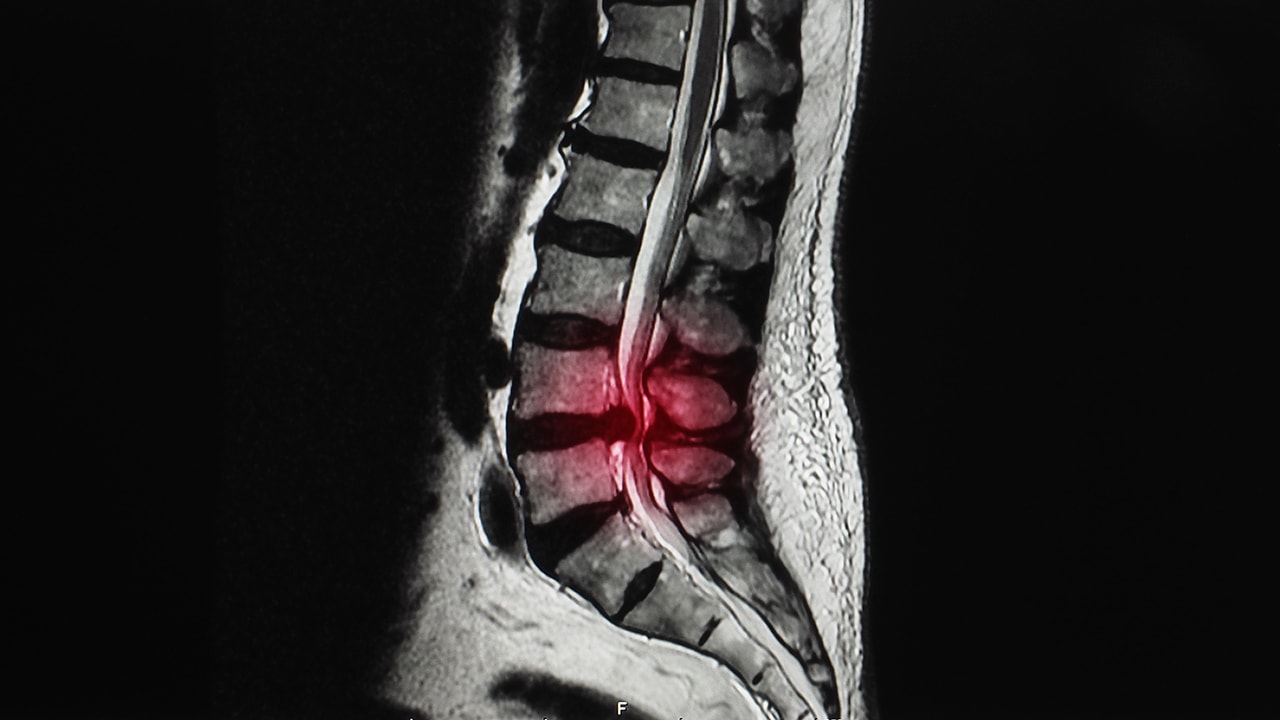

Seulontaohjelmat ovat osoittautuneet tehottomiksi esimerkiksi aivokasvainten havaitsemisessa, ja ne ovat varmasti hyödyttömiä selkärangan rappeuttavien tai kasvainten havaitsemisessa. Kuten olemme jo keskustelleet muissa artikkeleissa, selkärangan rappeuma ei sinänsä ole patologinen prosessi, vaan pikemminkin luonnollinen osa ihmisen biologiaa. Siksi ei ole järkevää tutkia potilaita, joilla ei ole neurologisia oireita tai kipuja. Tällaisissa tutkimuksissa havaitsemme välilevyjen ja fasettinivelten rappeutumista sekä joitakin muutoksia nikamien asennossa, jotka ovat normaaleja ikääntymisen merkkejä. Joskus potilas hakee apua lievän stenoosin diagnoosin vuoksi kaula- tai lannerangassa, mutta hänellä ei ole oireita. On vaikea selittää (ja usein vakuuttaa), että säännölliset kuvantamistutkimukset eivät ole tarpeen ja että potilaan tulisi hakeutua klinikalle vain, jos oireita ilmenee.

Vastaavasti lääketieteellisen avun laiminlyönti tai liian myöhäinen hakeutuminen hoitoon, kun oireet ovat jo ilmenneet, voi olla haitallista. Ajoittaiset selkäkivut, jotka häviävät itsestään, ovat normaaleja, mutta jatkuvat päänsäryt, jotka eivät häviä tavallisten kipulääkkeiden ottamisen jälkeen tai joihin liittyy muita oireita, kuten oksentelua tai näön hämärtymistä, eivät ole normaaleja. Lääketieteellistä apua on myös haettava, jos niska- tai alaselän kipu leviää terävänä, pistävänä kipuna tai pistelynä raajoissa. Harvemmin on haettava kiireellistä apua, jos tuntuu heikkoutta.

Vakavissa neurologisissa häiriöissä aika on ratkaiseva tekijä, ja varhainen tai kiireellinen diagnoosi ja kirurginen toimenpide voivat estää pysyvän vammautumisen. Itse asiassa, jos jalan menetys johtuu välilevytyrästä, leikkaus on suoritettava 48 tunnin kuluessa. Onneksi paljon harvinaisemmissa tapauksissa, joissa esiintyy sulkijalihaksen toimintahäiriö, leikkaus on suoritettava kiireellisesti.